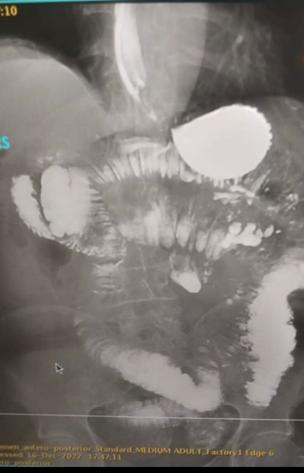

3. Uniform Requirements for Manuscripts Submitted to Biomedical Journals: Writing and Editing for Biomedical Publication. [Online].; 2006 [cited 2020 marzo 29. Available from: http://www.icmje.org/ recommendations/archives/2006_urm.pdf.

4. K. P. http://www.nlm.nih.gov/. [Online].; 2022. Available from: https://biblioteca.uah.es/investigacion/ documentos/Ejemplos-Vancouver-BUAH.pdf.